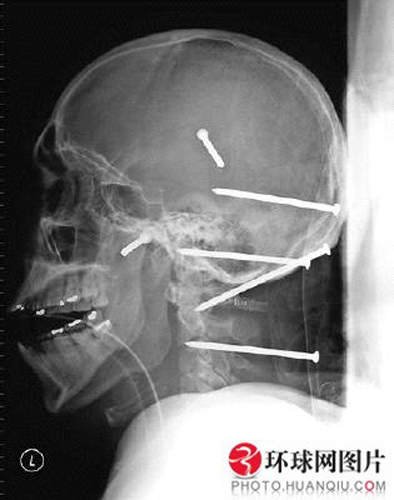

头部插入6根钉子却奇迹生还

目前梅加头部没有任何一根钉子,但在2004年,当他在屋顶施工时不小心从高处跌落。跌落的高度并不致命,致命的本应是插入颈部和头骨的6根3.5英寸长的钉子。但是他奇迹般活了下来,原来这几根钉子差一点就扎到了脑干脊髓。